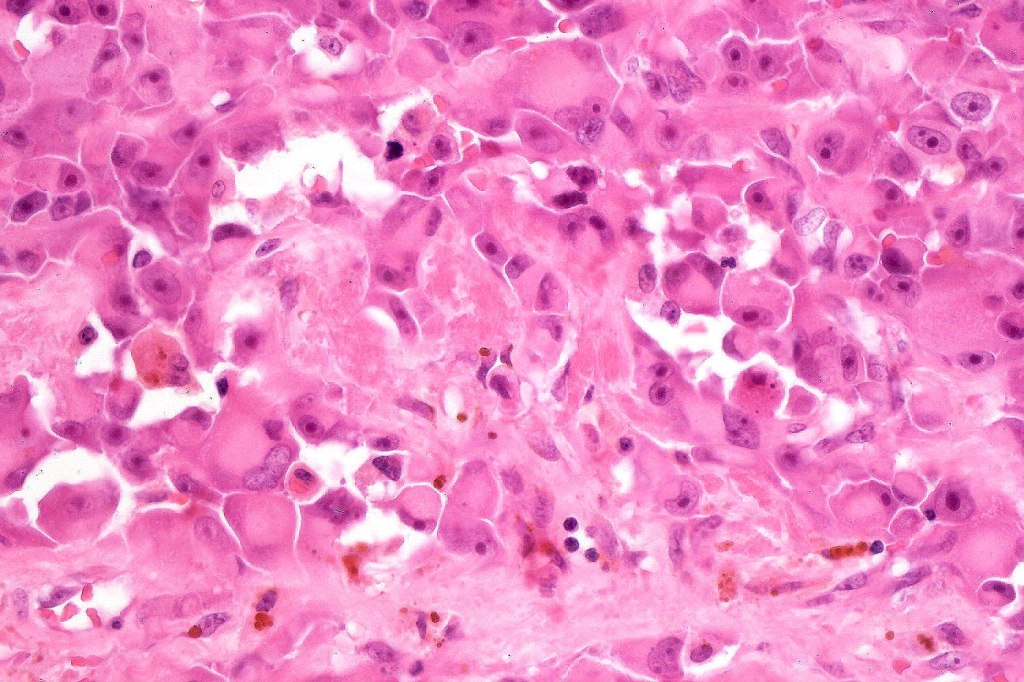

•Characterized by pleomorphic tumor cells with large eosinophilic, hyaline globular inclusions and eccentric vesicular nuclei containing prominent nucleoli, mitoses often conspicuous

•Very sparse melanin pigment may be identified